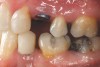

Figure 5j  A 50-year-old female concerned about appearance and bite. Jackscrew appliance was placed after 6 months of orthodontic alignment (A to C). Patient was missing No. 11 and had A-P and transverse maxillary deficiencies with anterior and left posterior crossbites. Bite was opened with glass ionomer cement. Single-tooth osteotomies were performed on Nos. 6 and 12 and multiple-tooth osteotomies were completed on Nos. 3 to 4, 7 to 10, and 13 to 14 (D). Corticotomies were also performed on Nos. 7 to 10 segment. Postsurgery 21 days (E). Jackscrews were activated 0.5 mm/day after 5-day latency period. Note pure translation of segments without tipping. Result 8 months postsurgery (F to I). Tooth No. 12 was converted to a canine, and an implant was placed in regenerate bone. Note amount of alveoloskeletal correction and increase in volume of maxillary arch. Also note in Figure 6C and Figure 6H the amount of protraction of maxillary anterior segments while anchorage was maintained in posterior segment. Restorative dentist: Michael E. Carter, DDS.

Figure 5j

Figure 6a  A 50-year-old female concerned about appearance and bite. Jackscrew appliance was placed after 6 months of orthodontic alignment.

Figure 6a

Figure 6b  A 50-year-old female concerned about appearance and bite. Jackscrew appliance was placed after 6 months of orthodontic alignment (A to C).

Figure 6b

Figure 6c  A 50-year-old female concerned about appearance and bite. Jackscrew appliance was placed after 6 months of orthodontic alignment (A to C).

Figure 6c

Figure 6d  Figure 6d Patient was missing tooth No. 11 and had A-P and transverse maxillary deficiencies with anterior and left posterior crossbites. Bite was opened with glass ionomer cement. Single-tooth osteotomies were performed on teeth Nos. 6 and 12 and multiple-tooth osteotomies were completed on teeth Nos. 3 to 4, 7 to 10, and 13 to 14.

Figure 6d

Figure 6e  A 50-year-old female concerned about appearance and bite. Jackscrew appliance was placed after 6 months of orthodontic alignment (E). Jackscrews were activated 0.5 mm/day after 5-day latency period. Note pure translation of segments without tipping.

Figure 6e

Figure 6f  Jackscrews were activated 0.5 mm/day after 5-day latency period. Note pure translation of segments without tipping. Result 8 months postsurgery. Tooth No. 12 was converted to a canine, and an implant was placed in regenerate bone. Note amount of alveoloskeletal correction and increase in volume of maxillary arch. Also note in Figure 6c and Figure 6c the amount of protraction of maxillary anterior segments while anchorage was maintained in posterior segment. Restorative dentist: Michael E. Carter, DDS.

Figure 6f

Figure 6g  Jackscrews were activated 0.5 mm/day after 5-day latency period. Note pure translation of segments without tipping. Result 8 months postsurgery. Tooth No. 12 was converted to a canine, and an implant was placed in regenerate bone. Note amount of alveoloskeletal correction and increase in volume of maxillary arch. Also note in Figure 6c and Figure 6c the amount of protraction of maxillary anterior segments while anchorage was maintained in posterior segment. Restorative dentist: Michael E. Carter, DDS.

Figure 6g

Figure 6h  Jackscrews were activated 0.5 mm/day after 5-day latency period. Note pure translation of segments without tipping. Result 8 months postsurgery. Tooth No. 12 was converted to a canine, and an implant was placed in regenerate bone. Note amount of alveoloskeletal correction and increase in volume of maxillary arch. Also note in Figure 6c and Figure 6c the amount of protraction of maxillary anterior segments while anchorage was maintained in posterior segment. Restorative dentist: Michael E. Carter, DDS.

Figure 6h

Figure 6i  Jackscrews were activated 0.5 mm/day after 5-day latency period. Note pure translation of segments without tipping. Result 8 months postsurgery. Tooth No. 12 was converted to a canine, and an implant was placed in regenerate bone. Note amount of alveoloskeletal correction and increase in volume of maxillary arch. Also note in Figure 6c and Figure 6c the amount of protraction of maxillary anterior segments while anchorage was maintained in posterior segment. Restorative dentist: Michael E. Carter, DDS.

Figure 6i